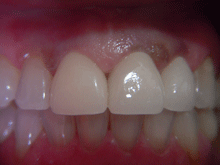

A G C

ガルバノテクニックを用いて作製されるセラミックであり、純金を用いる事によって生体親和性に優れ、歯肉にもやさしく、最適な適合精度と最適なマージン適合性が得られます。

症 例